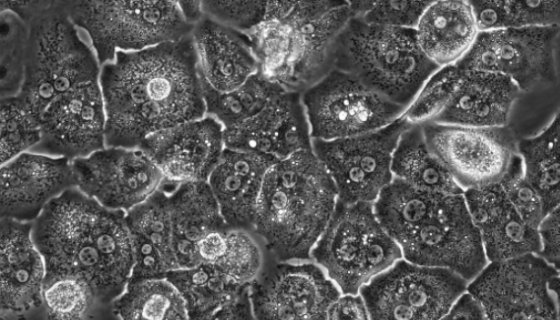

大鼠胰腺星状细胞的背景与应用!

大鼠胰腺星状细胞是胰腺外分泌腺所固有的细胞,主要存在于胰腺腺...